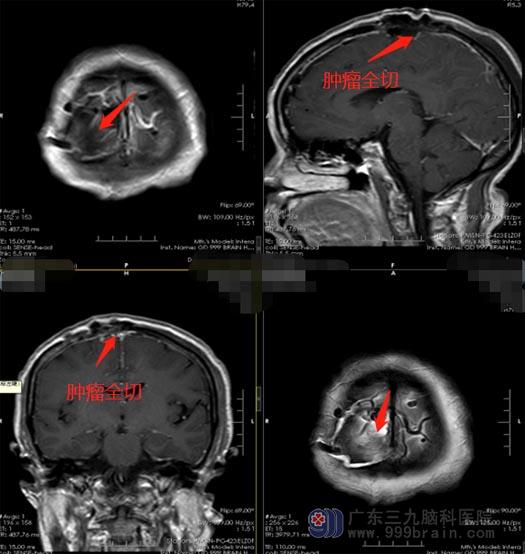

了解病情后,刘阿姨和女儿虽然是既宽心又担心,但她们还是积极地同意手术治疗。医院副院长、神经外五科主任鲁明带领手术团队在全麻下为阿姨施行“右顶部镰窦旁脑膜瘤切除术”,术中顺利将肿瘤全切除,术后恢复良好,没有出现手术并发症。

▲手术后